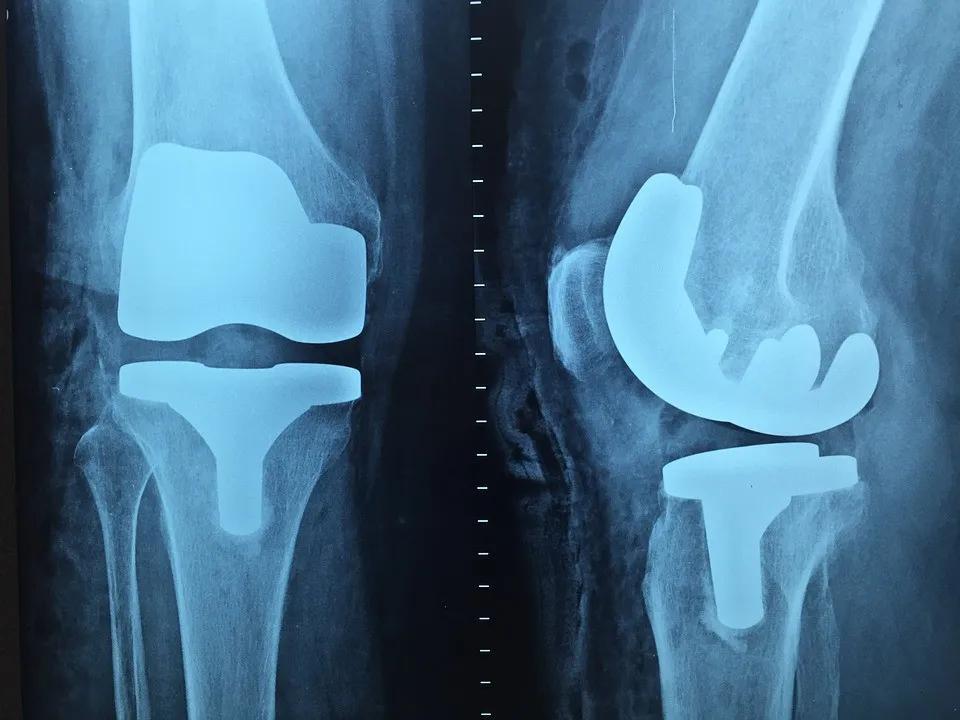

【建议】平时应尽可能多锻炼关节,发作时则要少活动,尽快接受抗菌药物治疗,畸形严重时应接受外科手术治疗。

在病情非常严重时,可能出现以萎缩为主的关节变形,同时还伴随有明显的肌肉萎缩现象。